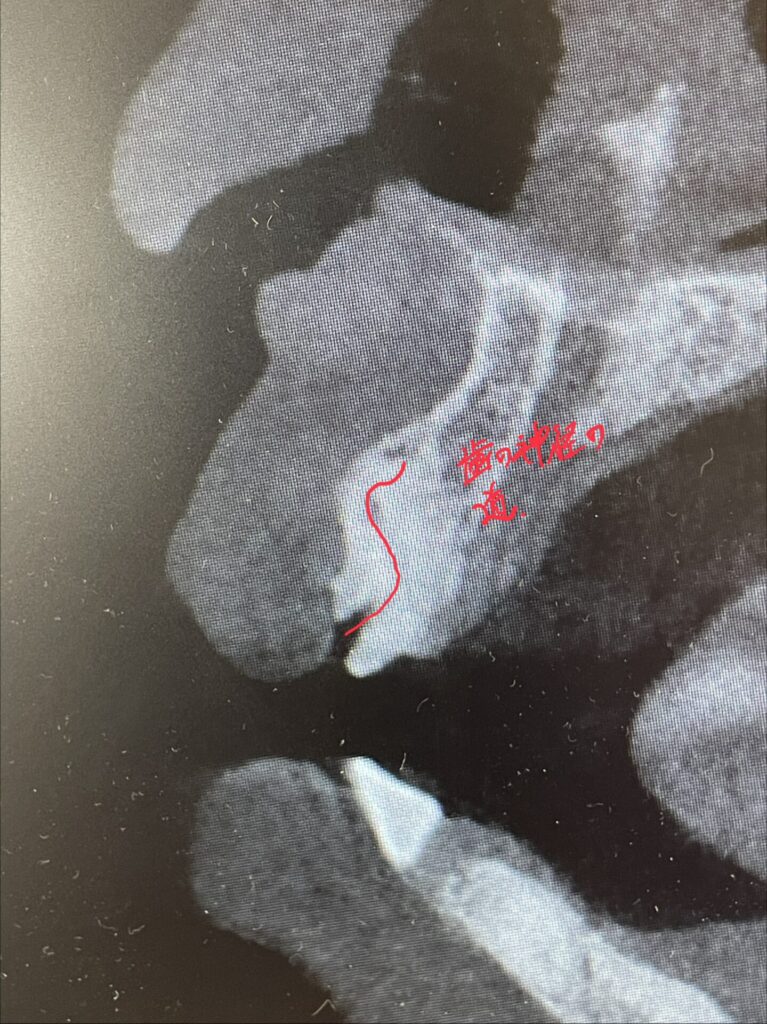

神経処置が未処置のまま放置?の歯です。実は下のCTの写真でわかる様に歯の変形があります。ご本人様にお伺いしたところ昔前歯を強打した経験があるとの事でしたが、当時は受診せず経過を診ていたそうです。セラミック治療した歯科ではこの変形した歯について何も伝えられなかったと。。。

ここからは私の推測ですが、、、神経の管の中にビタペックス(消毒効果のある根管充填材)の様なものが確認出来ました。神経治療をトライしてレッジを作ってしまい治療できなかったのでビタペックスを根充材として入れてレジンで蓋をしたのだろうと思います。

この歯については当院でもかなり時間をかけて慎重にマイクロスコープ下で治療のトライをしましたが根の先までは到達出来ませんでした。(これについてもちゃんと治療前に説明しています。今後の治療方針も事前に説明しており、経過が悪ければ歯根端切除や抜歯→インプラントかブリッジか入れ歯の補綴になる事ご了承済です)